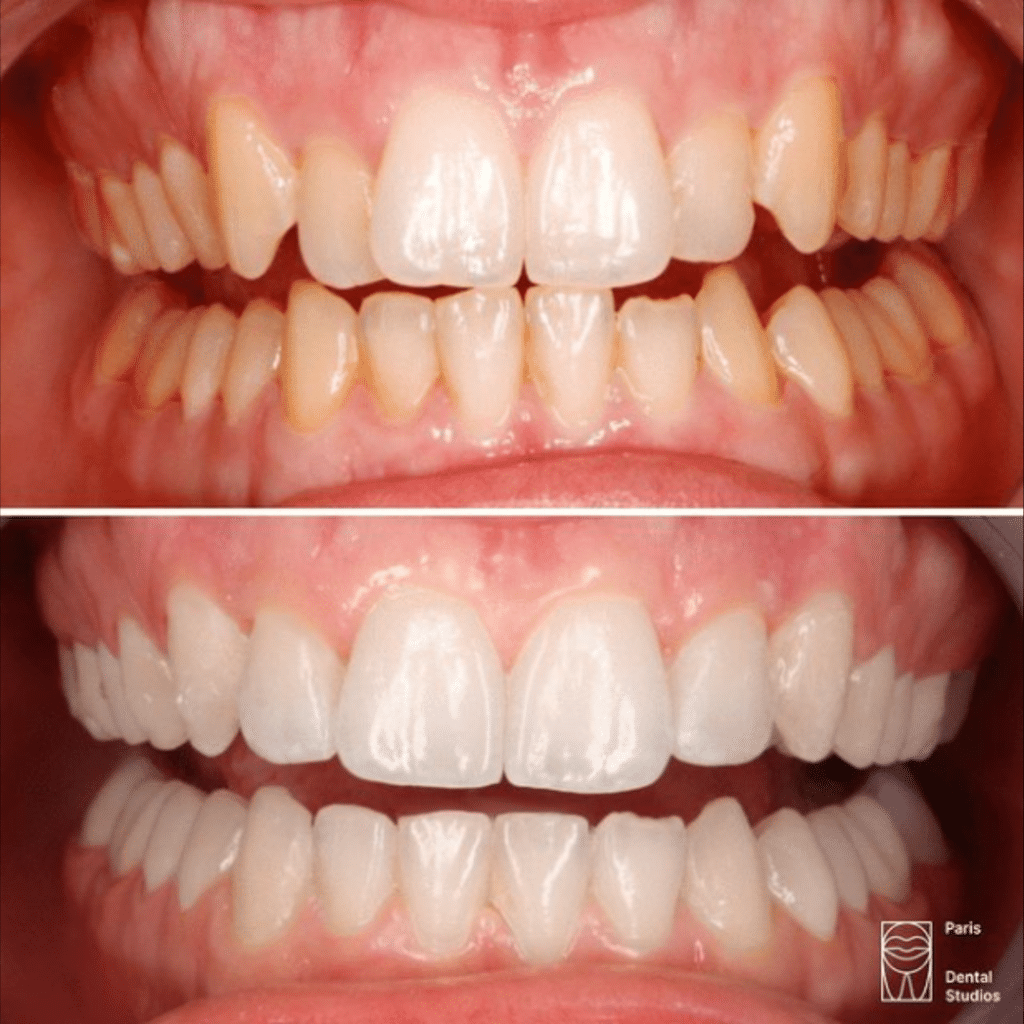

Supraclusion

dentaire

Maloclusion

La supracclusion : situation où les dents supérieures recouvrent excessivement les dents inférieures .

Nos résultats